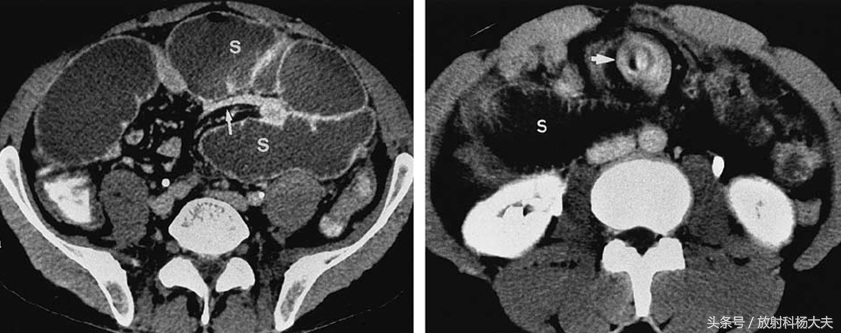

S代表扩张的肠管,左图白箭为鸟嘴征,右图为旋涡征

做完了后,我们在CT上看到了两个征象,鸟嘴征和旋涡征。所谓鸟嘴征就是扩张的肠管和萎陷的肠管的部位就像长长的鸟嘴;而旋涡征是肠系膜的血管在扭转后形成的,因此根据CT诊断为肠扭转。

所谓肠扭转是一段肠袢沿肠系膜长轴旋转或两段肠袢扭缠成结而造成闭袢性肠梗阻,前者常见。常常是因为肠袢及其系膜过长,肠扭转后肠腔受压而变窄,引起梗阻、扭转与压迫影响肠管的血液供应,因此,肠扭转所引起的肠梗阻多为绞窄性,而要判断肠管的血液情况,是否有肠缺血坏死,必须进行增强扫描。